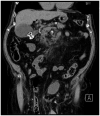

Introduction: The minimally invasive approach of endoscopic ultrasound (EUS)-guided procedures for cholecystocholedocholithiasis, such as EUS-guided gallbladder drainage (EUS-GBD), EUS-guided rendezvous (EUS-RV), and EUS-guided biliary drainage (EUS-BD), is affirmed as an effective treatment for patients with acute cholecystitis (AC) who are unfit for surgery and for patients with common bile duct stones (CBDSs) who have experienced a previous ERCP failure. Furthermore, in cases of difficult CBDS extraction during endoscopic retrograde cholangiopancreatography (ERCP), cholangioscopy-guided electrohydraulic lithotripsy (CS-EHL) has showed optimal results. The main objective of our study was to evaluate the effectiveness of EUS-GBD and percutaneous gallbladder drainage (PT-GBD) in patients with AC who are unfit for surgery. We also aimed to evaluate the efficacy of EUS-GBD, EUS-BD, and EUS-RV following ERCP failure and the effectiveness of CS-EHL for difficult CBDS extraction in our hospital. The secondary aim was to examine the safety of these procedures.

Materials and methods: We conducted a retrospective evaluation of all the EUS-GBD, PT-GBD, EUS-BD, EUS-RV, and CS-EHL procedures, which were prospectively collected in the gastroenterology and digestive endoscopy unit and the general surgery unit from January 2020 to June 2023. The efficacy was expressed in terms of technical and clinical success rates, while safety was assessed based on the rate of adverse events (AEs).

Results: We enrolled 83 patients with AC and high surgical risk. Among them, 57 patients (68.7%, 24/57 male, median age 85 ± 11 years) underwent EUS-GBD, and 26 (31.3%, 19/26 male, median age 83 ± 7 years) underwent PT-GBD. The technical and clinical success rates were 96.5 and 100% for EUS-GBD, and 96.1 and 92% for PT-GBD. The AEs for EUS-GBD were 1.7%, and for PT-GBD, it was 12%. ERCP for CBDS extraction failed in 77 patients. Among them, 73 patients (94.8%) underwent EUS-RV with technical and clinical success rates of 72.6% (53/73) and 100%, respectively. No AEs were reported. Four out of 77 patients were directly treated with EUS-BD for pyloric inflammatory stenosis. In 12 patients (16.4%), following unsuccessful EUS-RV with a CBD diameter ≥ 12 mm, an EUS-BD was performed. Both technical and clinical success rates for EUS-BD were 100%, and no AEs were reported. EUS-GBD was the treatment of choice for the remaining 8 (10.9%) patients after failure of both ERCP and EUS-RV. The procedure had high technical and clinical success rates (both at 100%), and no AEs were reported. The 12 difficult CBDS extraction treated with CS-EHL also showed high technical and clinical success rates (both at 100%), with no reported AEs.